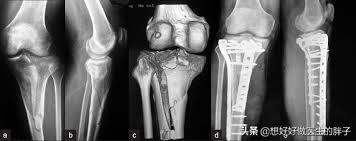

第一,一定要去复查骨折x线的情况,是否有明显的骨不连,也就是骨折没有愈合,骨折之间还存在着明显的松动,这样在活动的时候就会刺激骨折周边软组织等结构,导致肿胀不消退。另外七个月的时间,如果是手术治疗,是否存在折端的感染,在x线上也会有体现,长期的慢性感染也会导致肢体的肿胀,而且患者不一定会有明显发热等症状。

●如果存在骨不连的情况,7个月的时间对于胫腓骨粉碎骨折来说还不能说没有愈合的希望,因为这个位置由于其特有的血供特点,一旦骨折愈合就会比较慢,可以尝试去当地医院进行冲击波治疗,尤其是聚焦式冲击波治疗,对于骨不连有比较好的治疗效果,不需要2次开刀就有促进骨折愈合的疗效。目前有研究数据显示冲击波治疗骨不连有70%左右的愈合几率,所以建议还是先进行保守治疗三个月无效再考虑开刀手术治疗骨不连。而骨头愈合了,下肢稳定了,肿胀也就慢慢消退了!

胫腓骨这个位置一旦发生骨折,愈合也比较慢,肿胀消退比较慢,因为这个位置血运相对来讲不是特别的好,即使是体重比较大的人在小腿这个部位也是比较细的,尤其是在胫骨前方这个部位,一般都是皮包着骨头,一旦发生骨折恢复起来比较慢,也是可以理解的!但是7个月的时间如果仍然明显肿胀的话,一定要进行x线的检查以及下肢血管彩超的检查,明确是否有骨不连、骨折的感染或者是下肢血运的问问题。如果检查没有太大的问题,建议要科学的康复锻炼,同时平时注意减少下垂下肢的时间,可以口服一些促进肿胀消退的药物。